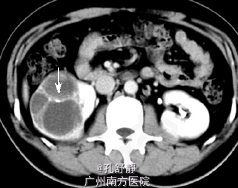

入院后查血肌酐为158umol/L,移植肾功能良好。腹部CT提示右肾巨大占位性病变,且分隔,考虑右肾肾癌。

诊断:右肾占位性病变,考虑右肾肾癌 处理:检查提示肾癌可能性大,跟患者和患者家属讨论后决定手术治疗,于是在入院后第3天在我院行右侧肾癌根治术,术后取活检确诊为肾癌,术后结合化疗。